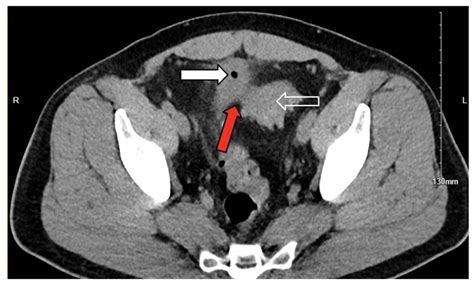

Diagnosing a colovesical fistula involves a combination of clinical evaluation, imaging studies, and sometimes endoscopic procedures. The diagnostic process typically includes:

• Imaging studies: CT scans, MRI, or barium enema can help visualize the fistula.